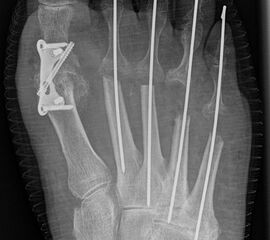

Deutlich bessere Ergebnisse wurden erreicht durch eine Kombination der OP nach Tillmann mit einer Arthrodese des Großzehengrundgelenks oder auch einer Lapidus-Arthrodese 611. Dies wurde bereits 1956 durch Vainio empfohlen, hat sich aber erst in diesem Jahrtausend flächendeckend durchgesetzt 121314.

Zum Lesen der Bildbeschreibung und zur Vollansicht bitte die Bilder anklicken.